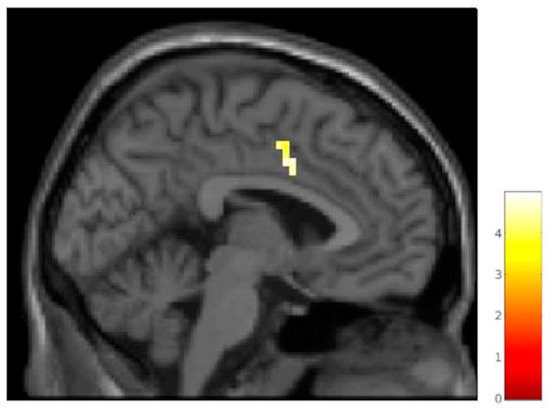

| pregenual anterior cingulate cortex | 32 | r/l | 125 | 3.59 | 12 | 38 | 6 | 12 | 38 | 12 |

| Mid-cingulate cortex | 24 | l | 15 | 4.68 | −3 | 2 | 38 | −3 | 4 | 35 |